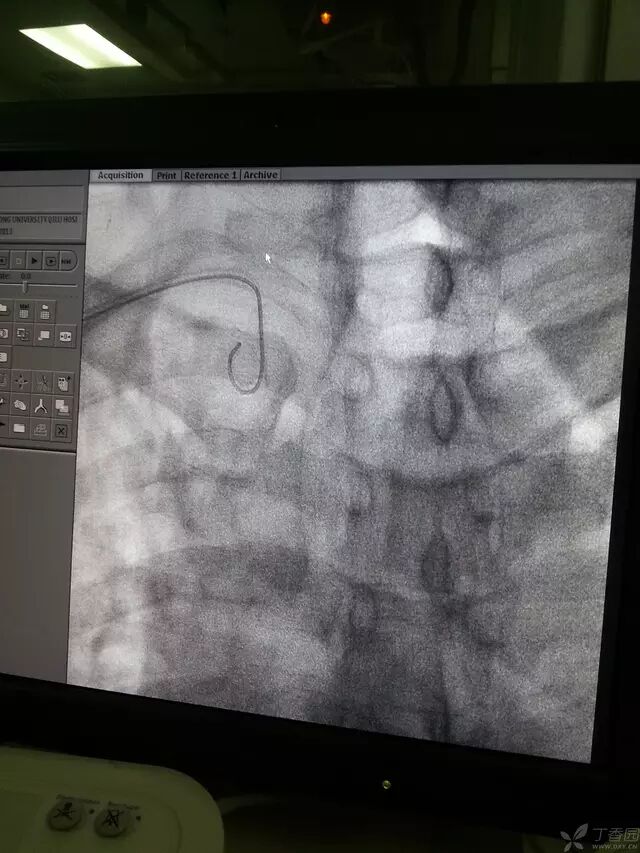

可嘱病人深吸气并憋住,一般导丝可顺利进入升主动脉,下降至窦底,使导丝盘成 L 型时,如下图。

造影导丝是什么原来心脏造影这样做:冠脉造影全程图解_https://www.jmylbn.com_新闻资讯_第12张

然后导管跟进,固定导丝,进入窦底,导管进入如图时可回撤导丝。

造影导丝是什么原来心脏造影这样做:冠脉造影全程图解_https://www.jmylbn.com_新闻资讯_第13张